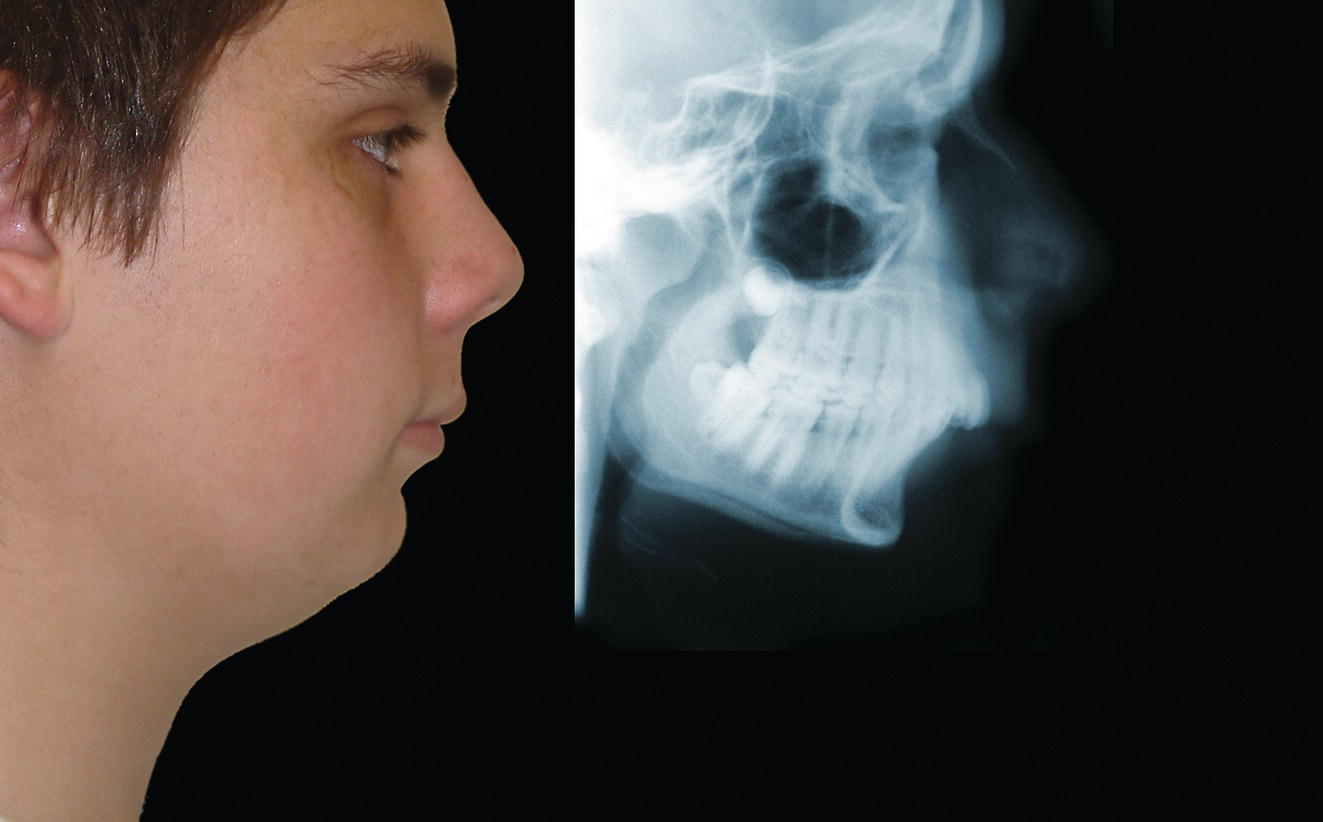

The morphology of the upper aspect of the neck and its transition with the submental region has a major impact on the aesthetics of the lower face. The anterior part of the neck extends no higher than the inferior border of the mandible. The hyoid bone is connected to the mandible by a thin sheet of muscle, the mylohyoids, which form the upper limit of the anterior part of the neck and separate the mouth from the neck. Superficially (i.e. below the mylohyoids) lies the anterior belly of digastric, while lying above it, half hidden under the mandible in the submandibular fossa, is the submandibular salivary gland (Figure 21.1). These structures are covered in by the investing layer of deep cervical fascia, which is attached to the hyoid bone and the inferior border of the mandible. The platysma muscle lies in the subcutaneous tissues. It forms a broad, flat sheet, extending from the deep fascia over the upper part of pectoralis major and the most anterior part of deltoid to the inferior border of the mandible, with some fibres reaching the lateral part of the lower lip. The sternocleidomastoid muscle forms a prominent neck landmark and may be made to stand out by turning the head towards the opposite side against resistance. The two heads of origin are from the sternum and medial one‐third of the clavicle; its attachment is to the mastoid process, which forms a readily visible and palpable bony landmark behind the lobe of the ear (Figure 21.2). Figure 21.1 Submental anatomy in relation to the mandible, with muscle attachments: Despite its importance in facial aesthetics, there is much confusion in terminology relating to the description and analysis of the submental‐cervical region. For example, the cervicomental angle has been described by perhaps half a dozen different methods, depending on the describing authority. Appropriate terminology is essential for the evaluation and accurate description of submental‐cervical aesthetics (Figure 21.3). Figure 21.2 Profile view of the face and neck with superimposed bony and muscular outlines: Cervical point (C‐point or ‘point C’): The innermost (posterior‐superior) point between the submental plane and the anterior aspect of the neck in the midsagittal plane, located at the intersection of lines drawn tangent to the submental region and the anterior neck. Submental plane: A plane or line constructed between the cervical point (C‐point) and the most inferior point on the chin (soft tissue menton, Me’). If C‐point cannot be defined, the submental plane is drawn tangent to the submental contour passing through soft tissue menton. The submental plane is referred to as the ‘throat’ plane by some authorities; the submental length (distance from C‐point to menton) is therefore sometimes referred to as the ‘throat length’. Cervical plane: A plane or line drawn tangent to the anterior soft tissue contour of the neck above and below the thyroid prominence. Figure 21.3 Submental plane, cervical plane and cervical point (C‐point). A thorough understanding of the aetiological factors involved in creating a poor aesthetic contour of the submental‐cervical region is required in order to diagnose and appropriately plan the correction of the aesthetic submental‐cervical angles and contour. The tonicity of the submental‐cervical skin, the muscular support of the neck, the isolated fatty deposits in the submental‐cervical region, the skeletal framework of the mandible and chin, and the spatial position of the hyoid bone are all important parameters in the aesthetic analysis of the submental‐cervical region. An undesirable submental‐cervical contour may result from: It is paramount that the clinical evaluation is undertaken with the patient in natural head position (NHP). Even a small degree of upward or downward tilting of the head must be avoided as it may have a profound effect on the contour of the submental‐cervical region. A number of parameters may be analysed in the clinical evaluation of the submental‐cervical region: Mandibular and/or chin deficiency in the sagittal plane, and/or posterior (downward and backward) rotation of the mandible, often secondary to vertical maxillary excess, may contribute to the undesirable aesthetic appearance of the submental‐cervical region (Figure 21.4). It is helpful to have the ‘Class II skeletal pattern’ patient posture the mandible forward to a more normal sagittal position, which will concurrently stretch the submental soft tissues. If this manoeuvre improves the submental‐cervical aesthetics visually, and tightens the submental soft tissues to palpation, then correction of the underlying skeletal discrepancy is likely to improve the submental‐cervical aesthetics (Figure 21.5). Figure 21.4 Class II jaw relationship due to mandibular deficiency and significant compensatory proclination of the mandibular incisor teeth; the submental‐cervical angle is increased. Figure 21.5 (A) Patient with Class II jaw relationship due to mandibular deficiency. (B) Posturing the mandible forward to a more normal sagittal position will concurrently stretch the submental soft tissues. Figure 21.6 Skin laxity test. The converse is also true. Surgical procedures to set back the mandible, or set down the maxilla causing posterior mandibular rotation, will tend to have undesirable consequences on submental‐cervical aesthetics (see Figure 19.22). The patient must be informed of these potential untoward consequences of orthognathic surgery, and should be advised of the possible future need for aesthetic surgical procedures of the submental‐cervical region. The laxity of the submental‐cervical skin may be evaluated by the skin laxity test: the clinician stands behind the patient and gently pulls the soft tissues upward and backward just inferior and anterior to the ear, simulating a neck lift (Figure 21.6). If the soft tissues are easily displaced upward there is increased laxity of the skin, termed redundant skin.1 If following this manoeuvre there is still submental fullness, the patient has redundant skin and excessive submental‐cervical adiposity. Reduced tonicity of the platysma may contribute significantly to submental fullness.2,3 In addition, the platysma muscle may or may not merge anatomically across the midline. Frequently, excessive submental fullness results not only from redundant skin but from the redundant medial borders of the platysma muscle that fail to meet in the midline. Increased submental‐cervical fat accumulation may be independent of generalized body fat; in some patients subcutaneous fat accumulation in this region may remain despite extensive weight loss. In younger patients the fat usually accumulates between the skin and the platysma muscle. In older patients, the fat may accumulate both deep and superficial to the platysma (Figure 21.9). The quantity of submental fat may be estimated by the submental pinch test: the submental soft tissues are gently gripped between the thumb and index finger.1 This manoeuvre should be performed with the patient both in NHP and with the head extended and contracting the platysma muscle; in this way the clinician may determine whether the submental fat is predominantly supraplatysmal or subplatysmal. Figure 21.7 Platysma view: With the head tilted slightly back in frontal view, grimacing and clenching the teeth will induce contraction of the platysma muscle. The muscular fascicles of the platysma become visible beneath the skin. Figure 21.8 Platysmal bands may be evident in repose in an ageing neck. Figure 21.9 Submental adiposity. Figure 21.10 The definition of the inferior border of the mandible is an important aesthetic parameter as it defines the demarcation between the face and neck. (Detail, Woman’s Head, Leonardo da Vinci, c. 1470–76, Galleria degli Uffizi, Florence.) The definition of the inferior border of the mandible, from the chin to the gonial angle, is an important aesthetic parameter, as it defines the demarcation between the face and neck (Figure 21.10). In frontal view, the transition from the upper aspect of the neck to the inferior border of the mandible has a subtle hourglass appearance, with its superior aspect being well defined by the concavity immediately below the inferior mandibular borders (Figure 21.11).1 The soft tissues of the neck normally closely adhere to the structures underlying them. Lack of definition of the inferior mandibular border may be due to increased soft tissue laxity, fat accumulation, mandibular/chin deficiency or hyoid bone sag. Figure 21.11 In frontal view, the transition from the upper aspect of the neck to the inferior border of the mandible has a subtle hourglass appearance. The submandibular salivary gland envelopes the posterior border of the mylohyoid muscle, half hidden in the submandibular fossa on the medial aspect of the mandible (see Figure 21.1). Submandibular fullness may result from an increase in size of the submandibular gland, laxity of the neck fascial layer or submandibular gland ptosis. Rhytidectomy and platysma plication address this problem indirectly by increasing the fascial support for the gland. However, patients may develop a more noticeable submandibular fullness as the removal of submental fat unmasks the ptotic gland. Partial or complete submandibular gland resection provides definite improvement of submandibular fullness resulting from glandular hypertrophy or ptosis, but may be considered too radical for a patient with a normal‐sized, ptotic submandibular gland. Guyuron et al.4 have described the basket submandibular gland suspension technique, directly supporting the gland onto the inner aspect of the inferior surface of the mandible with a strong piece of fascia. This technique helps eliminate submandibular fullness in patients with normal‐sized, ptotic glands. Resection remains the treatment of choice for the correction of glandular hypertrophy. Figure 21.12 Of the ‘six visual criteria’ of the profile view for ‘success in restoring the youthful neck’, the following are demonstrated: 1 Distinct inferior mandibular border 4 Visible anterior border of sternocleidomastoid muscle 5 Submental‐cervical (submental‐neck) angle between 105° and 120° 6 Sternocleidomastoid‐submental plane (SM‐SM) angle approximately 90°